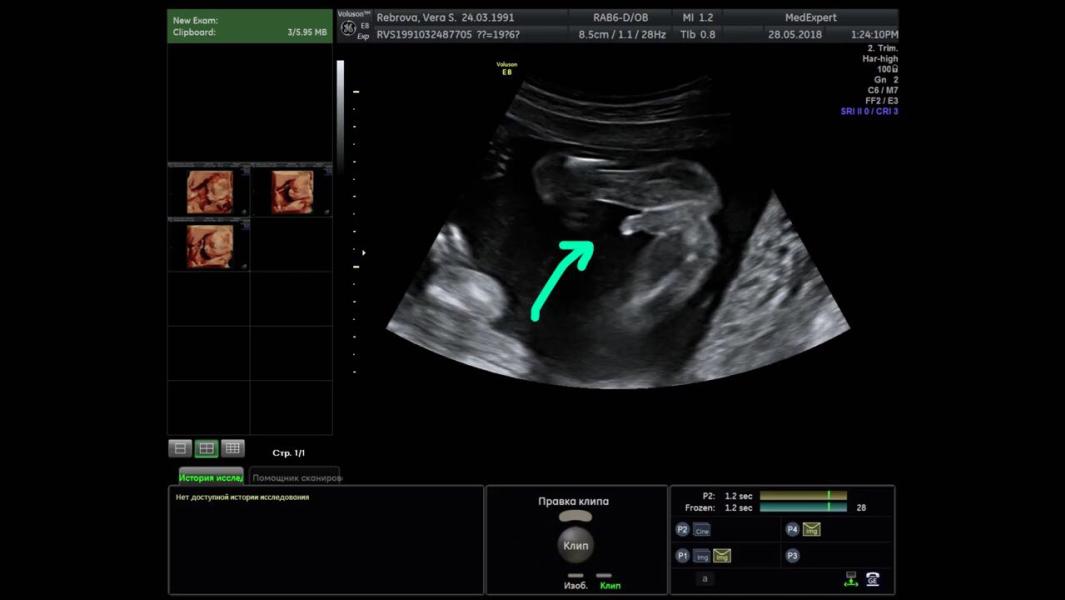

ВТОРОЙ СКРИНИНГ 💗 19 недель 6 дней

28.05.2018

Все УЗИ я всегда делала в перинатальном центре у Федотовой Т.В, но на момент второго скрининга она к моему сожалению ушла в длительный отпуск и ни «до» ни «после» по срокам я к ней никак не попадала. Тем не менее расстраивалась я недолго, так как в мыслях было пройти хоть раз 3D УЗИ где-нибудь на стороне 😄 выбор пал на Плотко И.С в платной клинике медэксперт. И почему-то я настороженно относилась к нему до этого момента, и пря...